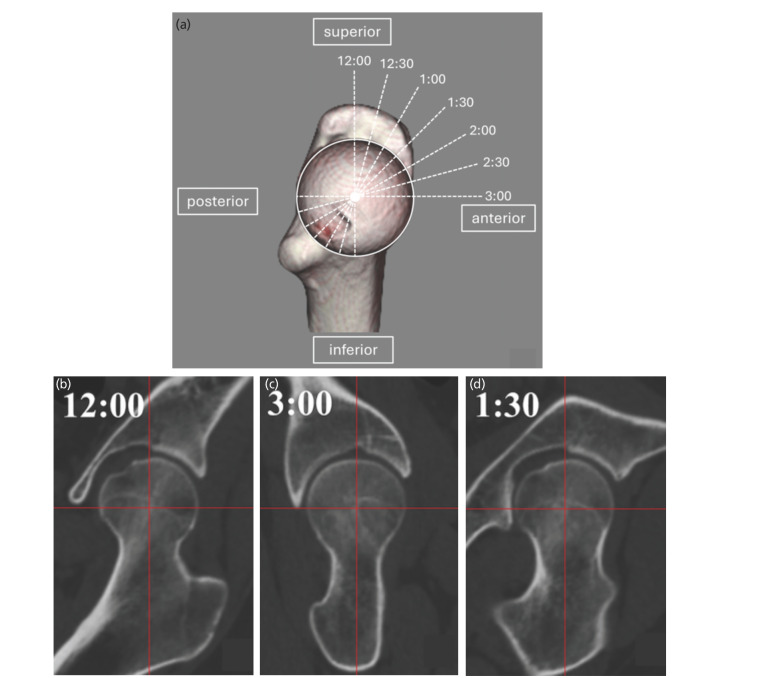

Materials and methods: This retrospective study included 57 patients with DDH (77 hips) who underwent PAO (DDH group). The control group comprised 30 patients (30 hips) with unilateral femoral head necrosis and contralateral unaffected hips (healthy hips). Coronal planes were created parallel to the femoral neck axis based on three-dimensional image analysis of hip computed tomography images. Coronal slices were obtained using clockwise rotation around the femoral neck axis in 15° increments, creating seven positions for measuring alpha (α)-angles. The superior and anterior directions were defined as 12 o'clock and 3 o'clock, respectively. Cam deformity was defined as an α-angle ≥60°. Outcome measurements were the α-angles of seven slices, cam deformity, and correlations between the maximum value of the α-angles and related factors.

Results: α-Angles were greater in the superior direction in the control than in the DDH group; conversely, they were greater in the anterior direction in the DDH than in the control group. The DDH group had more cam deformities than the control group. Cam deformities were more superior (12:30 to 1:00) in the control group, and more anterior (2:00 to 3:00) in the DDH group. Maximum α-angles in the DDH group correlated with superior acetabular coverage.